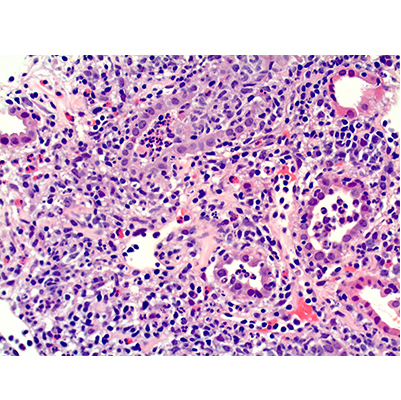

Interstitial nephritis is a kidney condition marked by inflammation and swelling of the spaces between the kidney tubules.

When these tubules become swollen, their function gets disrupted, leading to kidney-related problems that may range from mild to severe. Interstitial nephritis may be acute (sudden onset) or chronic (long-term).